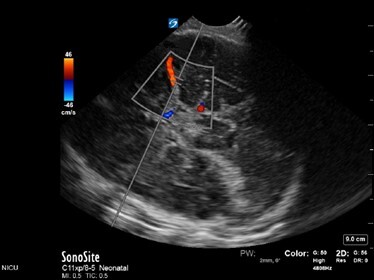

Neonatology Normal Anatomy Color Gate Not Parallel Angulation Image